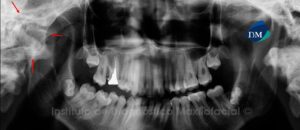

Las enfermedades cardiovasculares (ECV) abarcan un conjunto de afecciones que incluyen: la fiebre reumática / cardiopatía reumática, enfermedades hipertensivas, enfermedades cardíacas isquémicas (coronaria), enfermedad cardíaca